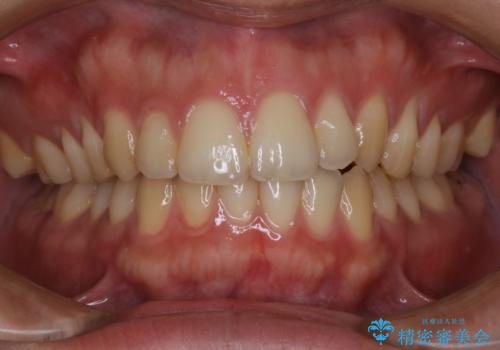

- マスクの着用により、以前より口臭が気になるとのことでした。しっかりと全体的なクリーニングを希望されたため、PMTC60分コースを行いました。

PMTCとはProfessinnal Mechanical Tooth Cleaning・専門器具による歯の機械的な清掃です。

バイオフィルム(細菌の塊)を破壊し、歯の表面をツルツルにすることでお口の中の細菌数を減らし歯周病のリスクが定着するのを防ぎます。更に、歯に新しい汚れがつきにくい状態になります。

バイオフィルムが除去されると、ご自身本来の歯の表面になります。PMTCをすることで口臭予防にもなり、定期的に行うことが大切です。